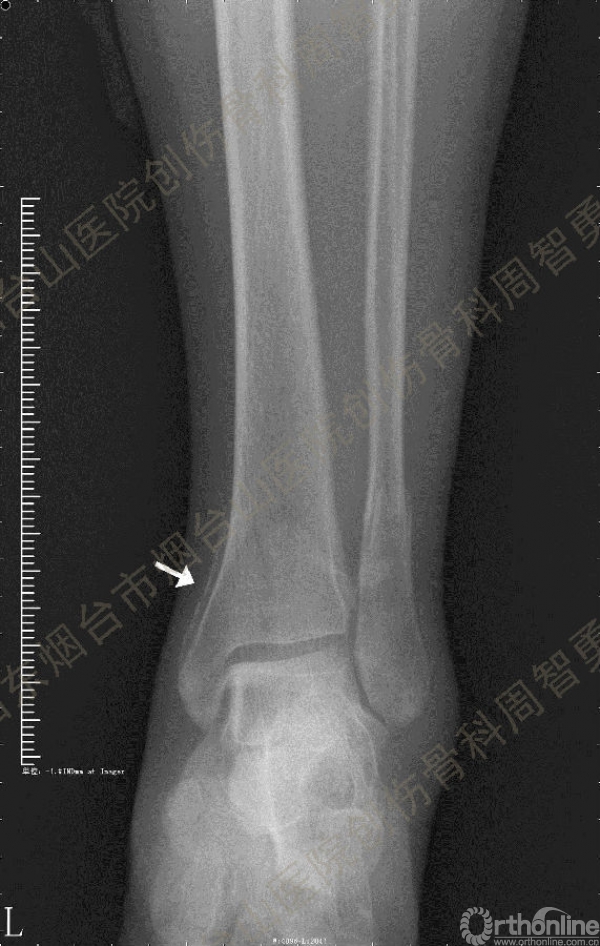

患者一般情况可,左踝关节肿胀,见皮下瘀斑,内、外、后侧有压痛,左踝关节主动运动受限,左足皮肤感觉、血供未见明显异常,左足趾各关节可主动运动。左踝关节正位X线片和CT重建示内踝内上方双层骨皮质影(图1a,c),CT示后侧骨折块分为后内侧骨折块和后外侧骨折块(图2a,b),后内侧骨折块累及内踝后丘,后丘骨折线呈冠状位(图2c),后内侧骨折块腹侧有向近端塌陷的小块骨软骨骨折块(图2d),CT也显示Chaput骨折块(图1c,2e)。

经典的后踝骨折发生于低能量旋转外力所致的踝关节骨折;标准pilon骨折见于高能量轴向暴力;而后侧pilon骨折是旋转外力和轴向暴力共同作用的结果,属于中等能量的损伤。踝关节骨折中的后踝骨折源自下胫腓后韧带的牵拉,骨折块位于后外侧,常为单一的三角形骨折块,大小从关节外片状骨折到累及胫骨远端关节面矢状径的40%(图4a)。后侧pilon骨折中的后侧骨折块较大,累及内踝后丘(三角韧带深层起点)在内的整个胫骨远端后侧,分为后内侧骨折块和后外侧骨折块,后内侧骨折块腹侧有向近端塌陷的骨软骨骨折块(图4b)。后侧pilon骨折中的内踝骨折线并不是水平位而是冠状位,可合并内踝前丘骨折。后侧pilon骨折踝关节正位X线片示特异性的内踝内上方双层骨皮质影(图1a,c)。这是由于后内侧骨折块的骨折线延伸到胫骨远端骨骺和干骺端的内侧骨皮质,其移位后的边缘成像所致。水平位CT显示后侧骨折块分为后内侧骨折块和后外侧骨折块,矢状位CT示后内侧骨折块腹侧有向近端塌陷的骨软骨骨折块。

③影像表现:踝关节正位X片显示特异性的内踝内上方双层骨皮质影

↑图 1a

↑图 1b

图 1 术前左踝关节正侧位X线片和CT重建,箭头所示内踝内上方双层骨皮质影(a,c)